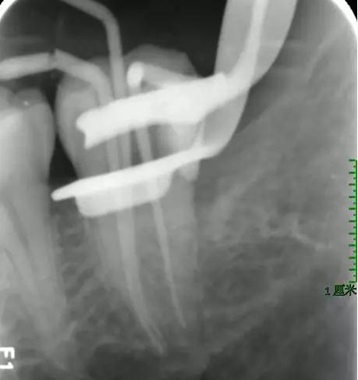

圖7 試主尖X線片

本病例根管充填過程(熱牙膠+iroot sp垂直加壓充填)